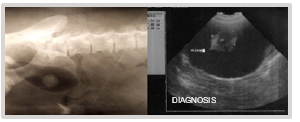

This case involves a 9-year-old female mixed-breed canine, referred for intermittent mild hematuric cystitis. Clinical examination of the abdominal cavity through palpation reveals the presence of a painless, immobile mass with a semi-soft and fixed consistency within the bladder. The ultrasonographic diagnosis reveals the presence of a heterogeneous element with irregular borders and a hypoechoic center, attached to the ventral wall and near the vesical neck, measuring 1.90 cm x 1.85 cm (Figure 1).

Figure 1 Ultrasonographic diagnosis of bladder: Heterogeneous element with irregular borders measuring 1.90 cm x 1.85 cm.

The cryosurgical option was suggested, but the owner declined. Four months later, during a follow-up ultrasound examination, an increase in the mass to 2.90 cm x 2.50 cm was confirmed (Figure 2). Faced with this situation, the owner agreed to the intervention.

Figure 2 Ultrasonographic diagnosis of bladder four months later: Increased mass measuring 2.90 cm x 2.50 cm.

The patient, a 9-year-old female Great Dane canine, presents with intermittent clinical signs of cystitis. Urine culture confirms its bacterial origin. The established antibiotic therapy is ineffective. The diagnosis is reconsidered. The ultrasound report indicates the presence of two closely spaced hyperechoic images, one measuring 1.61 cm x 1.16 cm and the other measuring 1.40 cm x 1.08 cm, implanted in the dorsal wall of the fundus of the urinary bladder. They involve 1/3 of its thickness (Figure 19). A laparotomy and cystotomy are performed, and the tumor is exposed through the ventral surface of the bladder using the "glove finger" maneuver.

Figure 19 Ultrasonographic Image: 2 closely spaced, hyperechoic masses in the bladder measuring 1.61 cm x 1.16 cm and 1.40 cm x 1.08 cm.

The medical treatment initiated for over two months fails to yield a favorable outcome. The diagnosis is reassessed. Contrast radiography and ultrasonography are requested. The reports indicate an irregularly shaped image, fixed to the ventral fundic wall, non-infiltrative, granular in appearance, with a diameter of 2.28 cm x 1.23 cm, compatible with a neoplasm (Figure 27).

Figure 27 Pneumocystography and ultrasonography indicate an irregular image of 2.28 cm x 1.23 cm, fixed to the ventral fundic wall of the bladder.